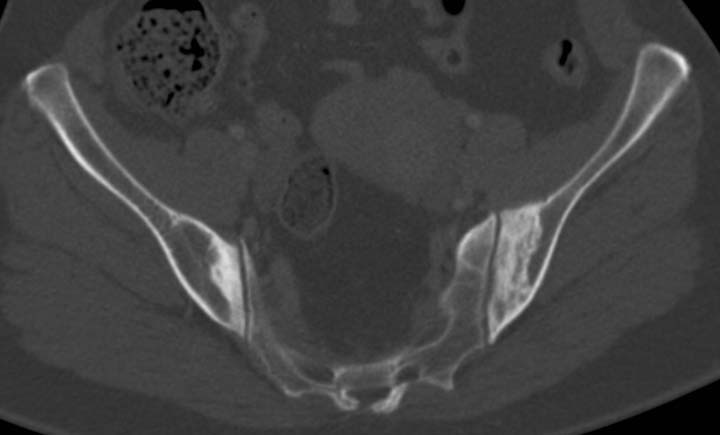

Osteitis condensans ilii is identiifed as benign sclerosis of the ilium adjacent to the sacroiliac joint. It is typically bilateral and symmetrical, and tends to be triangular in shape. This radiological abnormality is thought to be a benign reflection of bone remodelling with response to stress (increased radiologic density indicative of sclerosis) the sacroiliac joint itself is normal with no irregularity, erosions or loss of joint space.

It is most commonly seen in multiparous females; the underlying aetiology is believed to be mechanical stress across the sacroiliac joint. It is usually asymptomatic but uncommonly may cause lower back pain. The differential diagnosis is sacroiliitis, and rarely bone infection.